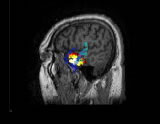

多模式神經(jīng)(腦)影像、腦活動源精確定位、2D/3D影像,CURRY是功能非常強大的電磁溯源分析定位和可視化工具,該軟件在世界上處于最領(lǐng)先地位,推動了神經(jīng)(腦)影像的飛速發(fā)展。

CURRY軟件包含多種功能,可以充分整合各種影像數(shù)據(jù)格式(EEG、MEG、MRI、fMRI、CT等)。通過將腦電活動與各種自發(fā)或功能影像數(shù)據(jù)的有機融合,CURRY為腦活動源的定位和分析提供了強有力的工具。CURRY可以利用MR和CT等得到的真實解剖結(jié)構(gòu)影像,建立每個被試的顱骨和腦的3D模型(該模型對探明神經(jīng)活動的發(fā)生源至關(guān)重要)。CURRY還可以將功能影像(如fMRI)和EEG、MEG的溯源重建進(jìn)行比較,以增強結(jié)果的準(zhǔn)確性。 CURRY可以在PC機、工作站、Laptops等運行,不僅可以用于研究工作(如腦的功能成像),而且,其強大的功能和先進(jìn)性使其具有了更為廣泛的應(yīng)用(如臨床、功能評估等)。

CURRY可以清晰地呈現(xiàn)具有高分辨率的各種影像及3D 重建結(jié)果(皮層、顱骨、頭皮、皮層斷層)。同時,可以觀察3D影像結(jié)果的動態(tài)變化(如3D Movie),具有很高的時間分辨率,也可以進(jìn)行體積測量。